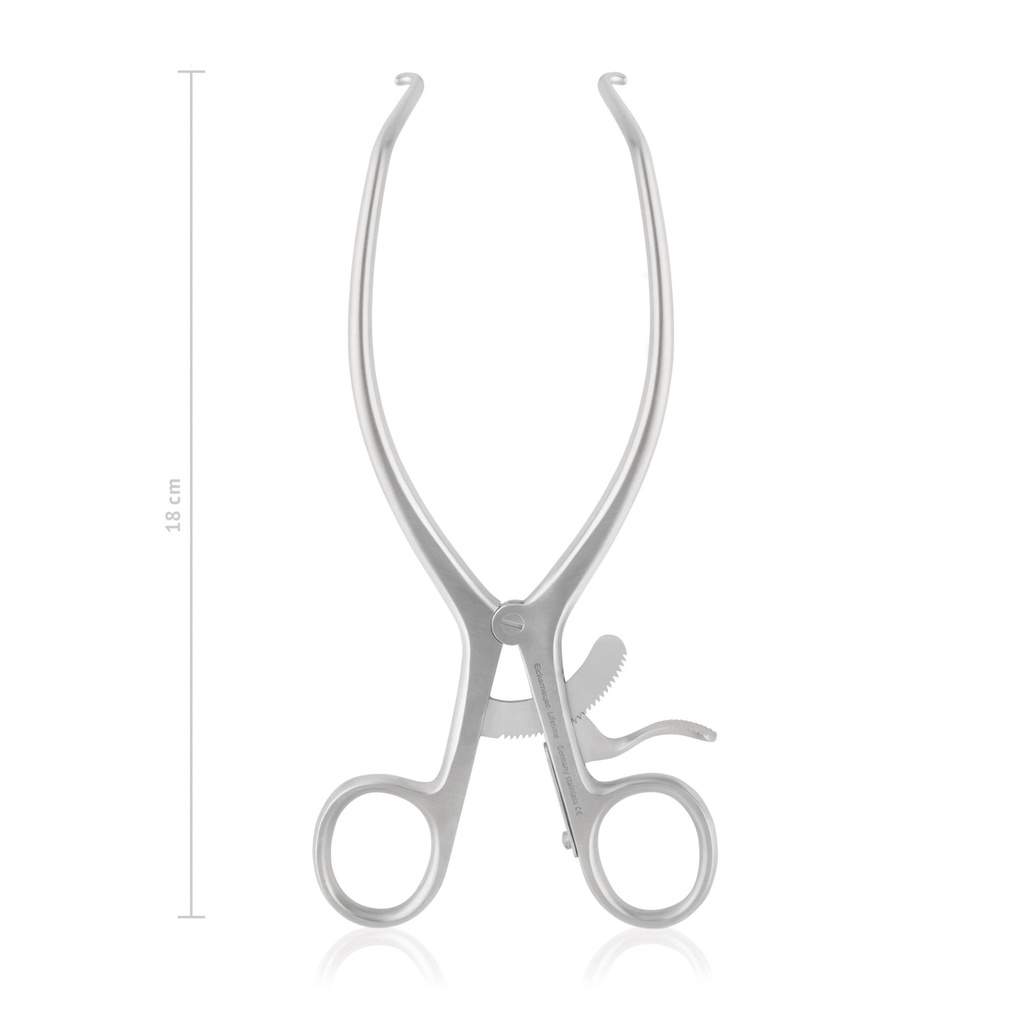

Retractor Gelpi, Self retaining, blunt, 18 cm

- Gelpi retractors are indispensable for orthopaedic procedures

- Its cam ratchet mechanism (self-locking) allows the surgeon to have both hands free

- We recommend a pair of same sized Gelpis to help maintain tissue retraction